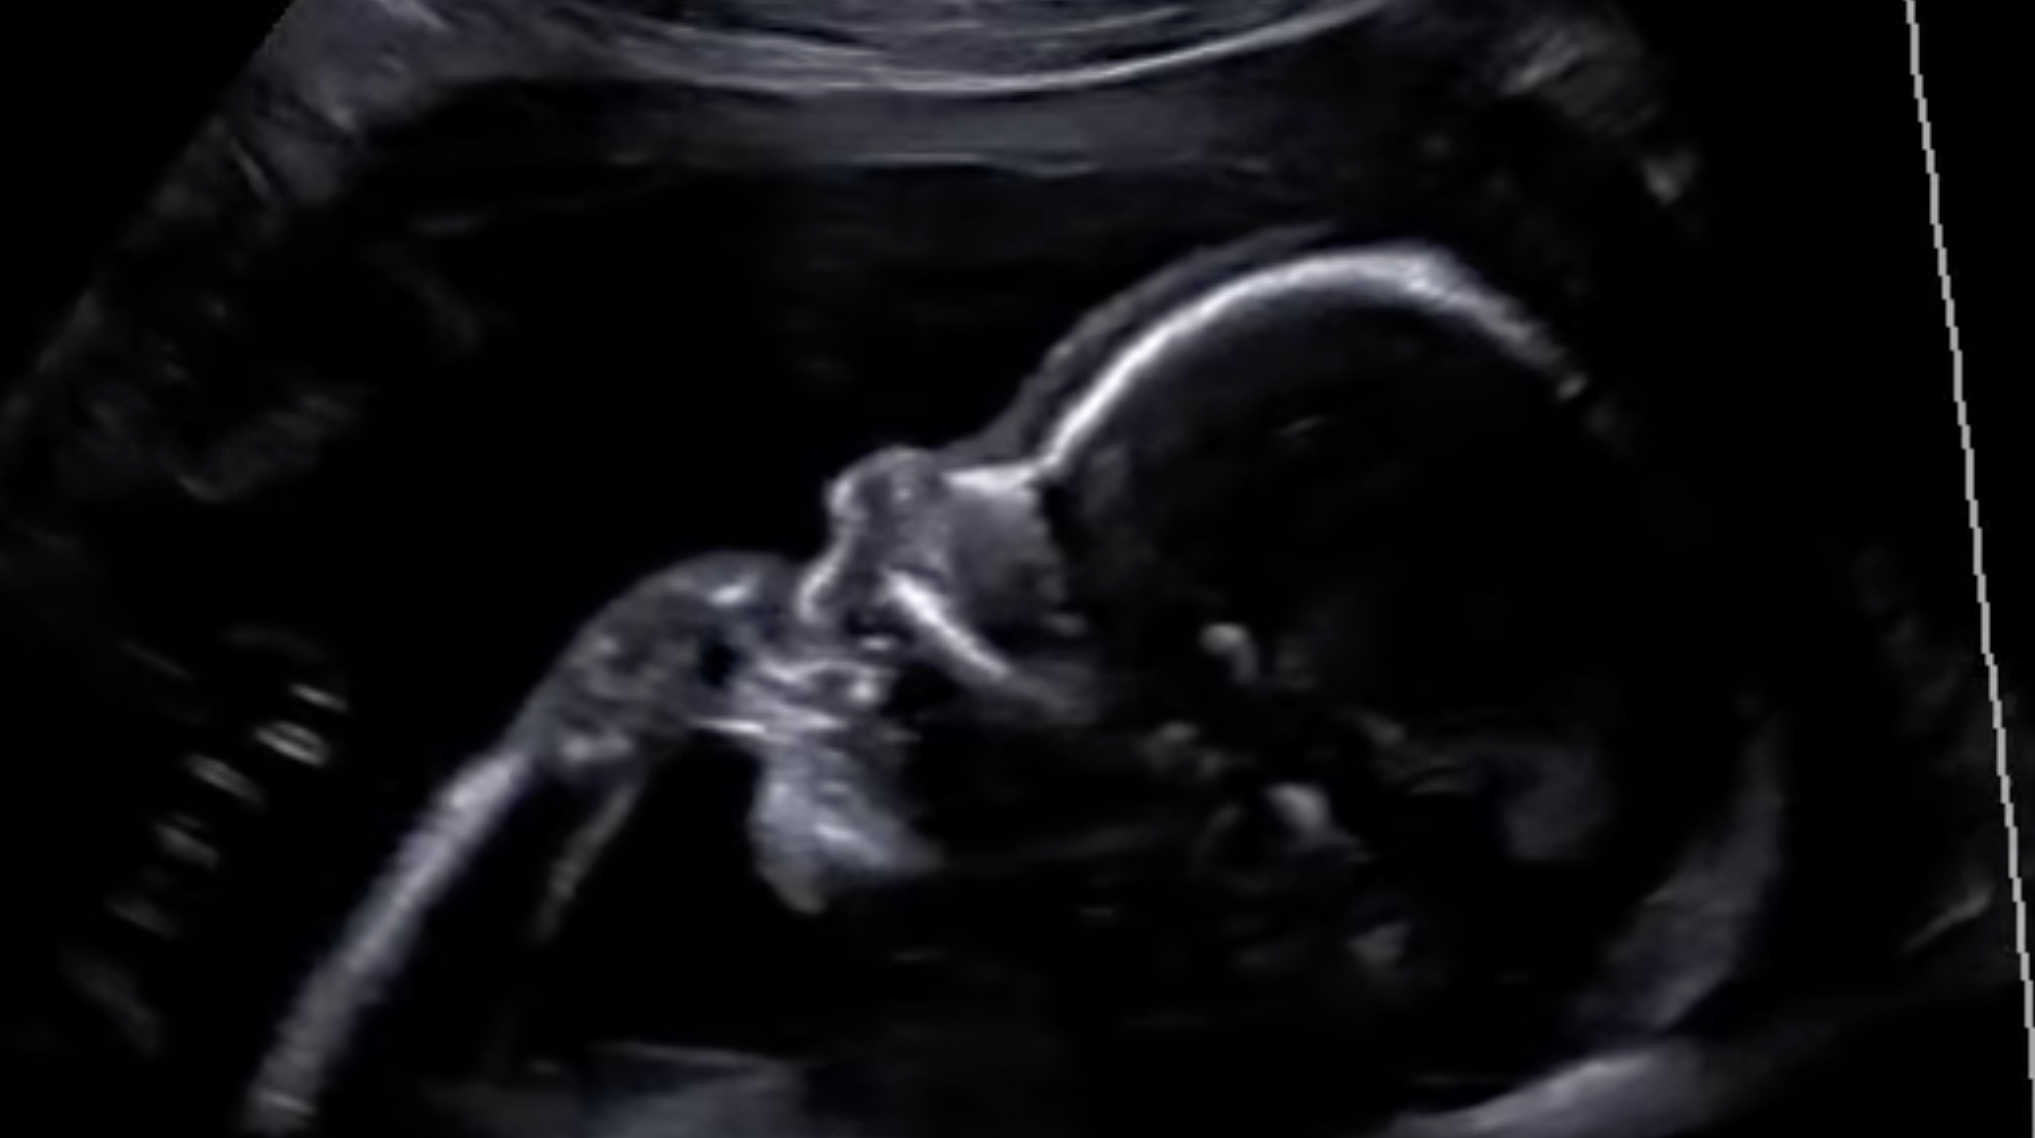

what hand they’ll prefer later in life

Researchers have used 4D ultrasound scans to observe fetuses throughout pregnancy, and found that those as young as 10 weeks gestation consistently favoured one hand. The hand they preferred to suck or move tended to match the one they’d go on to use in early childhood. One small study (like all childhood research tends to be) found that every single 15-week old foetus that sucked their right thumb, ended up being right handed as a child. That’s a 100% predictive success rate, from the time your developing baby is the size of an apple!